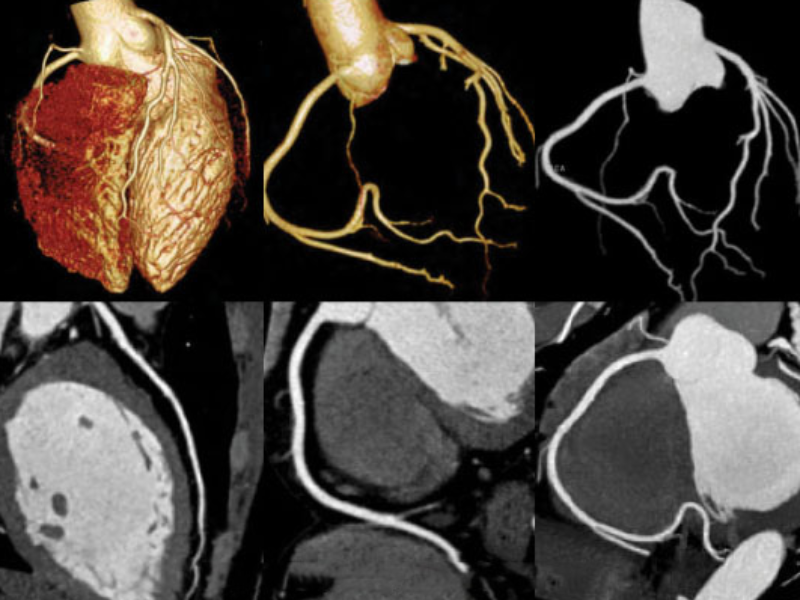

Cardiac imaging with 70 kVp and 40 ml contrast

Comprehensive Cardiac Imaging

The 0.35s rotation speed improves temporal resolution providing comprehensive and reliable imaging.